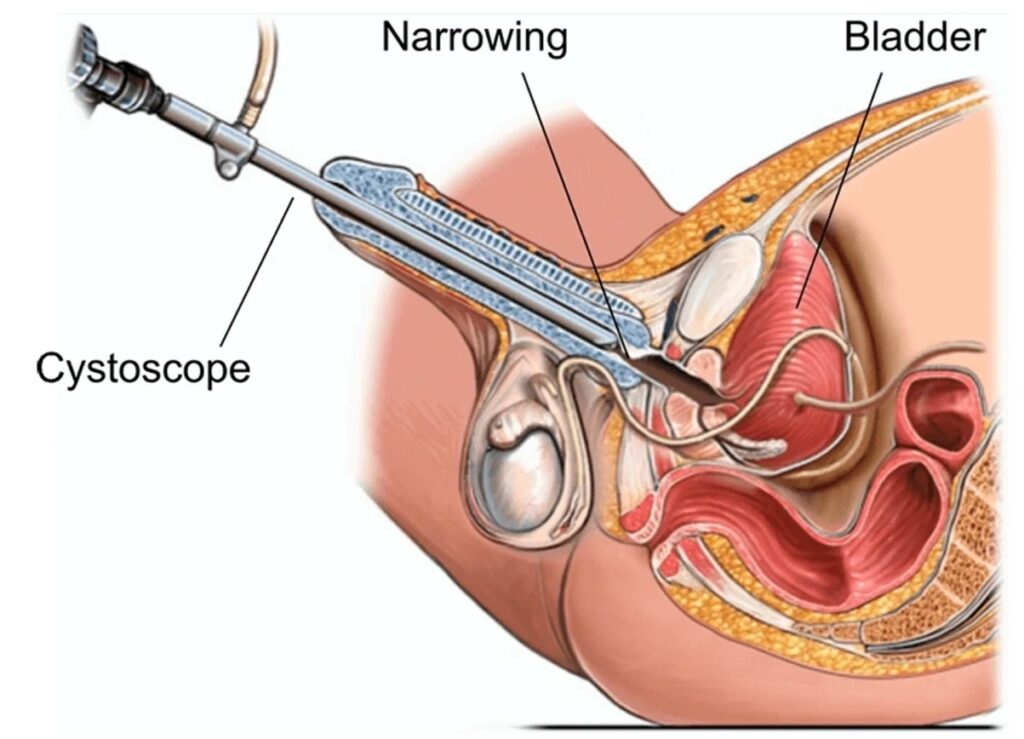

ENUCLEAÇÃO DE PRÓSTATA COM LASER HOLMIUM (HOLEP)

A HoLEP (Holmium Laser Enucleation of the Prostate) é uma técnica moderna e minimamente invasiva para o tratamento do **crescimento benigno da próstata (HPB – Hiperplasia Prostática Benigna).

💡 Por que optar pelo HoLEP?

✅ Procedimento com alta precisão e segurança

✅ Menos sangramento e recuperação mais rápida

✅ Preserva a função urinária e sexual

✅ Excelente opção para próstatas de grande volume

👨⚕️Indicado para pacientes que enfrentam sintomas urinários persistentes, o HoLEP oferece uma solução eficaz e definitiva, garantindo mais qualidade de vida!

📅 Agende sua avaliação e conheça essa inovação no tratamento da HPB! Sua saúde merece o melhor da tecnologia.